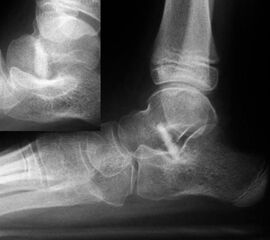

• Operation nach Dennyson-Fulforth mit Spongiosa oder Knochenspan (Bild 27)

Unter-/Überkorrektur, Horizontalisierung des Talus mit Impingement im oberen Sprunggelenk, Spandislokation (Bild 28), Pseudarthrose, Spanresorption (Bild 29), Korrekturverlust. Fraktur durch die Spanentnahmestelle (insbesondere an der prox. Tibia), Verkürzung der Fibula mit nachfolgender Valgusdeformität des oberen Sprunggelenkes (bei Verwendung eines Fibulaspans), langfristig Überlastung der Nachbargelenke 129.